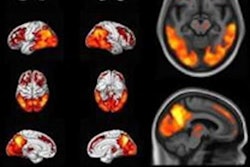

The group analyzed rates of change in brain metabolism among the groups based on standardized uptake value (SUV) ratios of F-18 FDG radiotracer. In addition, they tracked clinical progression of disease based on Clinical Dementia Rating Sum of Boxes (CDR-SB) scores, a measure of dementia severity based on cognitive impairment.

According to the findings, patients with MCI-LB had a faster decline in F-18 FDG SUV ratios compared with participants without cognitive impairment, specifically in the posterior cingulate, occipital, parietal, temporal, and lateral frontal cortices. The same regions showed greater metabolic decline in patients with DLB than in participants without cognitive impairment.

In addition, the rates of metabolic changes in F-18 FDG-PET in these brain regions correlated with the clinical measurements of disease progression, the authors explained.